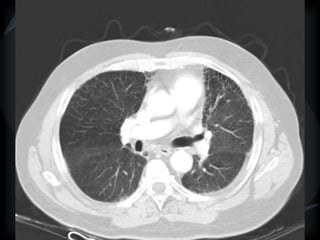

METS

random

Wegener’s

miliary